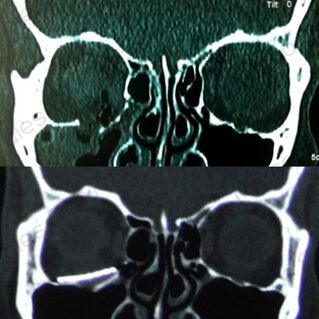

ÓRBITA

FRACTURAS ORBITARIAS